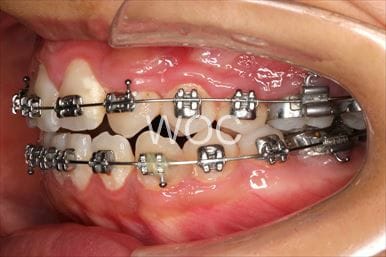

治療中1

治療中2

治療中3

治療中4

治療中5

- 年齢:17歳女性

- 主訴:出っ歯、前歯のガタガタが気になる

- 基本矯正料金:78万円

- 治療期間:1年2ヶ月

- 抜歯部位:上顎両側第一小臼歯